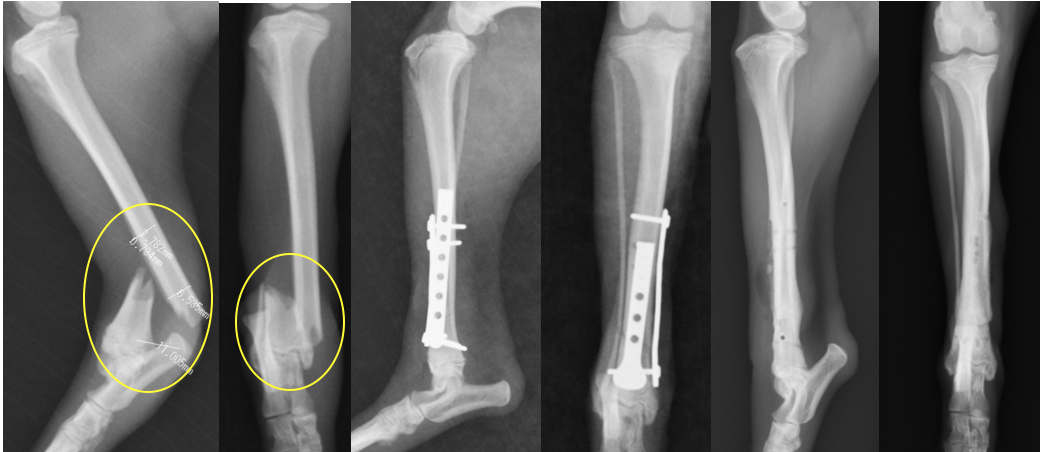

脛骨遠位のら線状骨折です。2枚のプレートで固定しています。この部位は軟部組織が少ないため、開放骨折になったり、治癒が遅れることがあるため、注意が必要です。

大腿骨近位の斜骨折です。斜骨折をラグスクリューである程度固定し、プレートによって支持する(守る)方法を使っています。これを中和プレートと呼ぶこともあります。